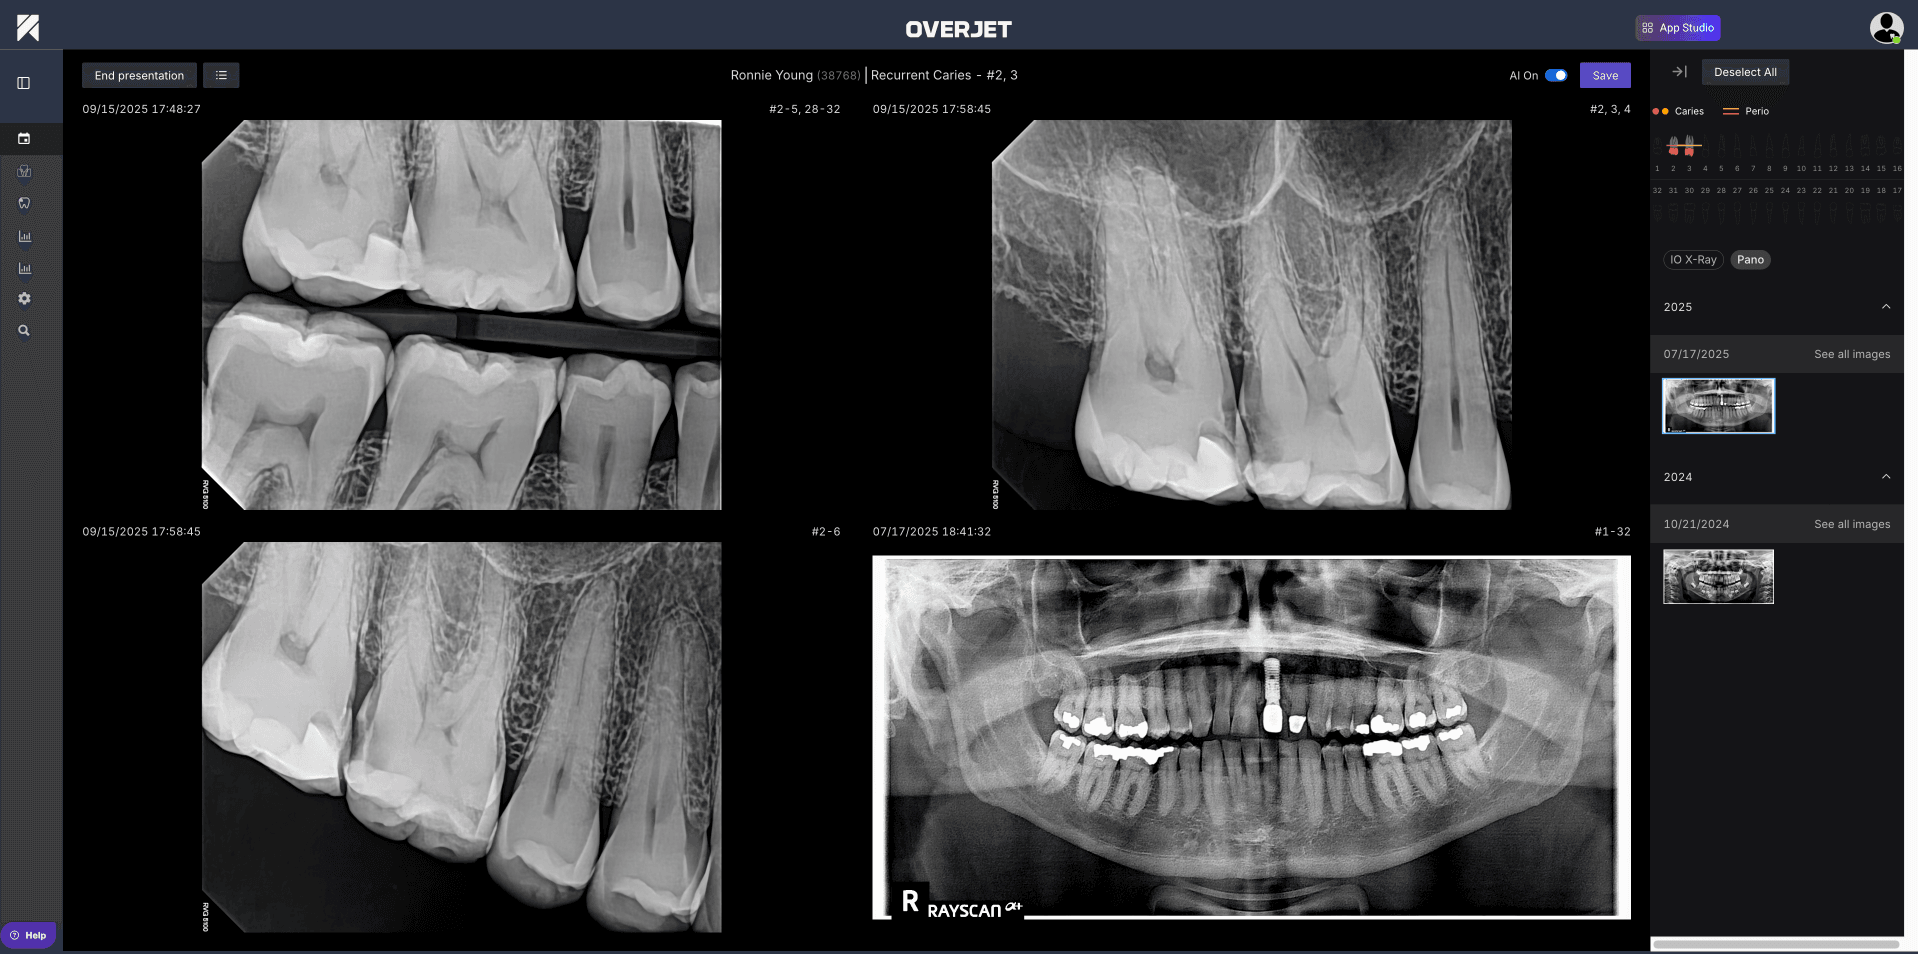

The ability to compare baseline and current images side by side proves particularly valuable for tracking disease progression or treatment outcomes over time. Toggle controls allow overlays to be shown or hidden during chairside conversations, giving clinicians flexibility in how they present findings to patients.

Visual communication transforms abstract dental concepts into understandable information, and AI overlays with millimeter labels make it easier to "show what you see" during patient conversations. Simple scripts for explaining caries, PARL, or bone loss—paired with printouts or emailed visuals—boost understanding and build trust through transparency.

The impact of these visual aids extends beyond education to treatment acceptance. Overjet AI Annotations have been shown to increase case acceptance by 25%, directly addressing the longstanding challenge of effectively communicating findings and motivating patients to accept recommended care. This improvement stems from patients' ability to see and understand their conditions clearly, making treatment recommendations feel less abstract and more necessary.

Clear visuals and well-crafted scripts turn complex diagnostic data into actionable conversations that patients can understand and act upon.